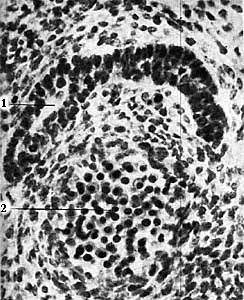

Ductus thyreoglossus в корне языка. Зародыш длиной 10 мм.

1 - ductus thyreoglossus; 2 - дуга аорты.